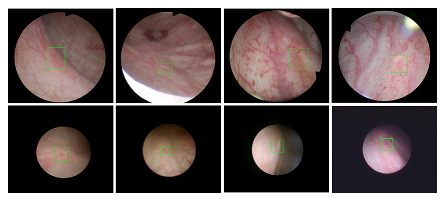

上海交通大学医疗机器人研究院—深睿医疗人工智能医学视频联合实验室成立于2018年7月。PI包括来自于六合宝典 和电院的三位教授,平台建设目标是将人工智能实时地用到临床医学中去,研究方向包括:1. 建立内窥镜人工智能辅助诊断系统,通过对病灶和解剖结构的实时识别来辅助医生更好地进行微创诊断和治疗;2. 以个性化、定量化的精准诊疗技术为研发目标,重点开展医学影像智能诊断、医学可视化及计算机辅助手术规划、AI及大数据分析在临床诊疗流程中的集成应用等方向的研发。试图利用AI技术、大数据分析技术、3D打印技术、虚拟现实及增强现实技术促进临床的影像诊断、治疗方案设计、预后预测分析等诊疗环节的智能化提升与技术变革;3. 面向运动医学康复、神经退行性疾病量化诊断,以及其他与人体运动相关的疾病诊疗、康复应用,开展视觉三维人体运动的测量、分析与识别研究,通过基于深度学习的视觉检测识别以及相关大数据分析,为相关疾病的诊疗和康复提供AI辅助。具体临床应用包括:关节镜手术术后康复指导和评估、帕金森病的量化诊断、精神疾病的量化诊断与评估、儿童异常行为分析等。

近年来,联合实验室发展了泌尿镜手术实时识别技术,人体姿态精确识别技术,另外围绕小儿先心病手术、肝癌消融手术、数字口腔诊疗的智能化提升等内容进行应用研发。